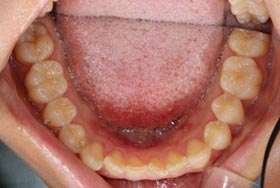

下記は、他院で虫歯と判断された患者様の症例です。

一見すると、奥歯の溝が虫歯になっているように見えます。しかし、ダイアグノデントによる診断では、虫歯治療が必要な数値を示しませんでした。つまり、歯を削る必要がないということです。